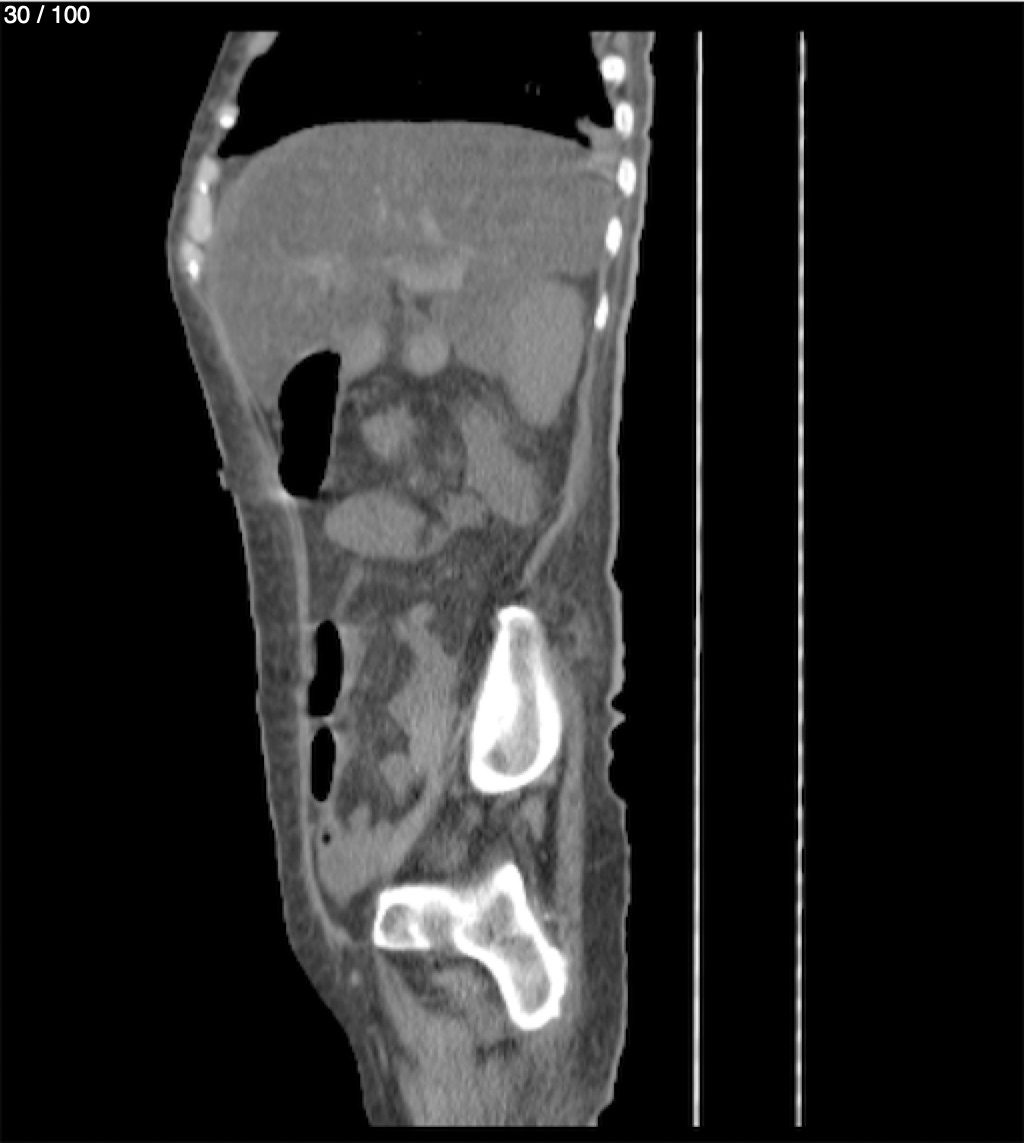

Hilda Geronimo Mendez 60A - T.C Abdomen Simple